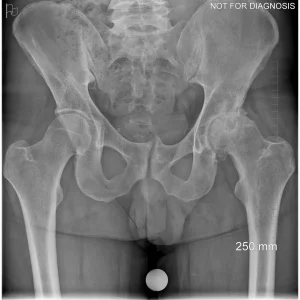

Hip resurfacing is a type of hip surgery used to treat hip arthritis, most commonly in younger and more active patients. Unlike a total hip replacement, hip resurfacing preserves more of your natural thigh bone. Instead of removing the entire femoral head (ball at the top of the thigh bone), the damaged surface is trimmed and covered with a smooth metal cap. The hip’s socket on the pelvis is also fitted with a metal cup.

The goal of hip resurfacing is to relieve pain, restore function, and allow a return to an active lifestyle while preserving bone for potential future surgery.